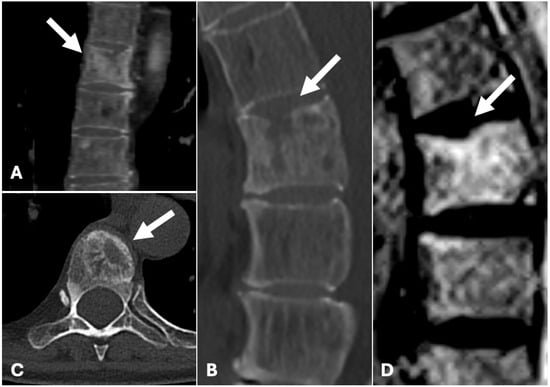

2. Case Presentation